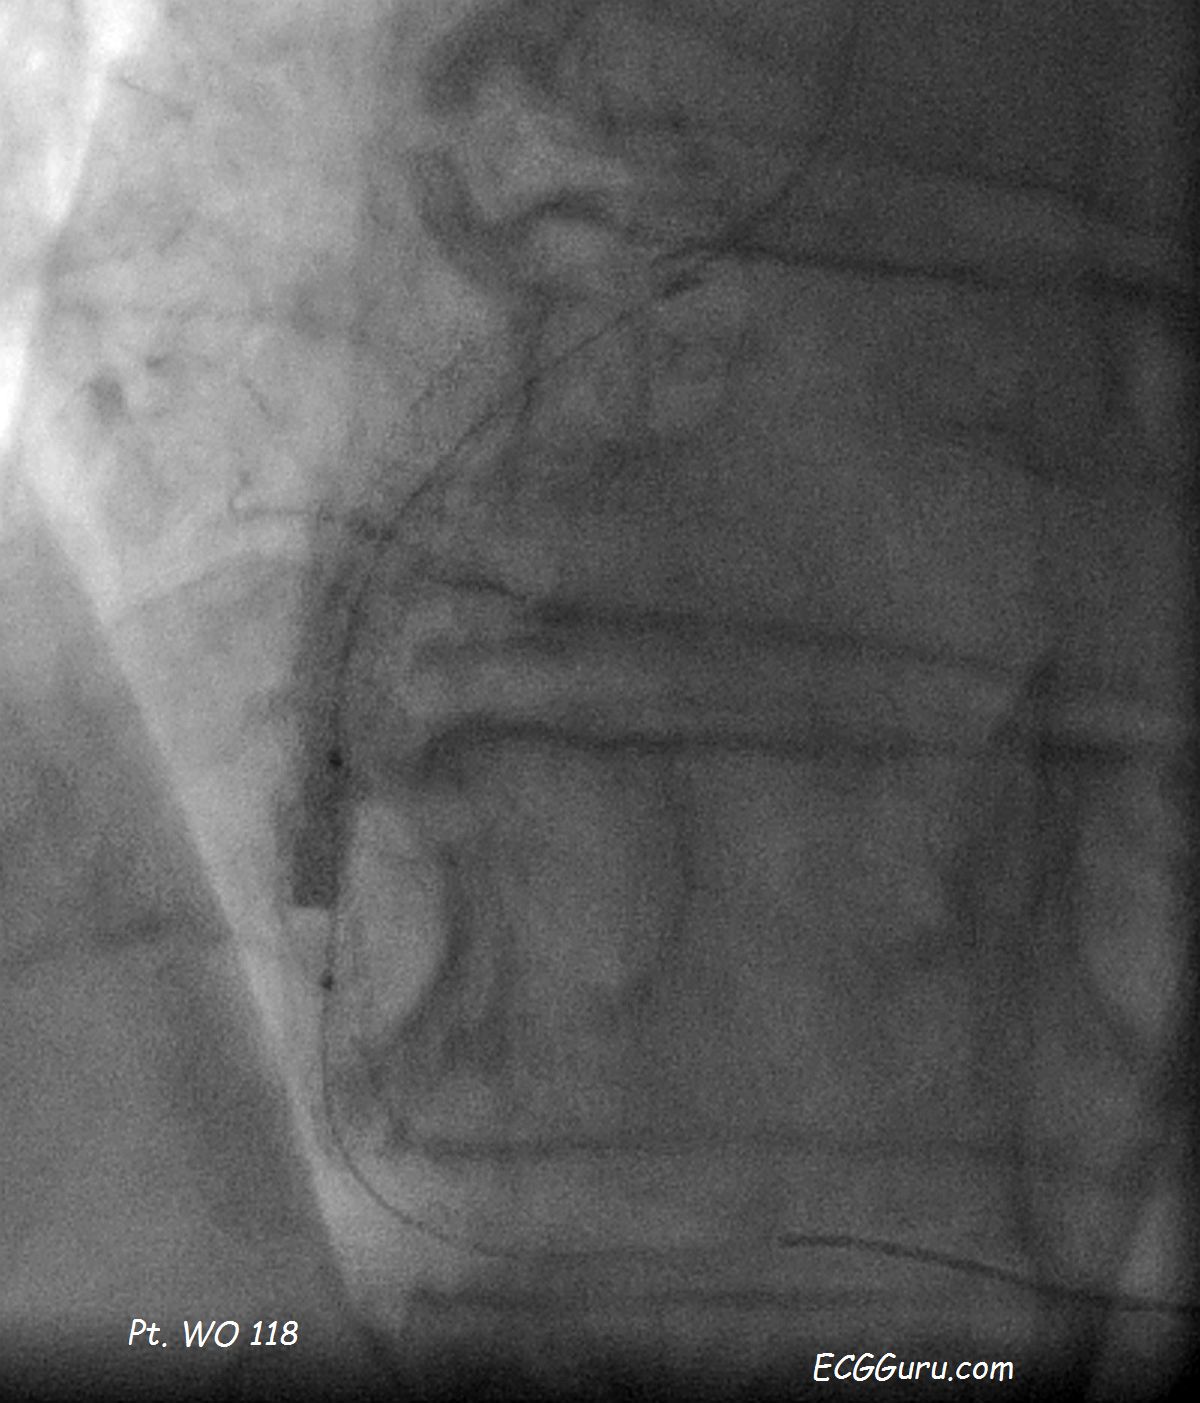

Patient WO 118 - Angioplasty of Right Coronary Artery

Angioplasty images from Patient WO 118, an 83-year-old woman with chest pain and near-syncope.